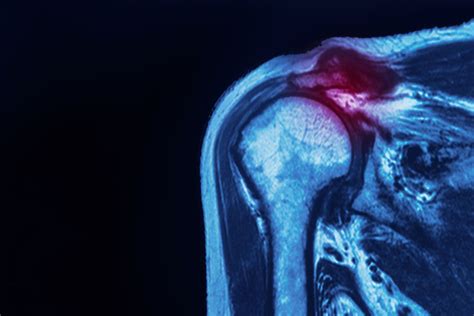

Ignoring ripped rotator cuff symptoms is rarely a good strategy. If your shoulder pain does not improve with a few days of rest, or if the pain is severe enough to interrupt your daily life, professional assessment is necessary. A healthcare provider will typically perform a physical examination to test the strength and range of motion in your shoulder. In many cases, diagnostic imaging such as an X-ray or MRI may be ordered to confirm the presence and size of a tear. Early detection often allows for non-surgical treatments, such as physical therapy, to be highly effective.